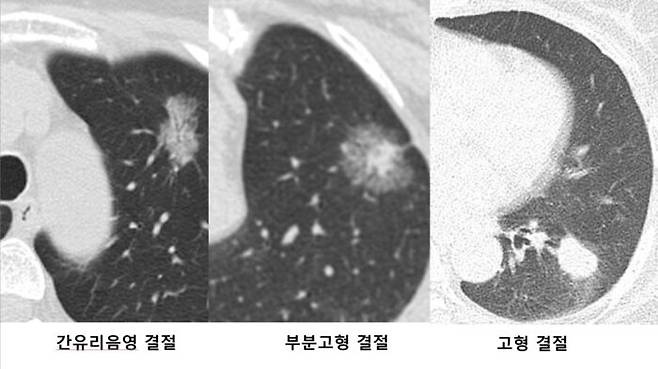

결절을 CT로 보면 전체가 균일하고 선명하게 보인다. 이를 '고형' 결절이라 한다. 반면 뿌옇게 보이는 경우를 '간유리 음영' 결절이라 불러 구분한다. 투명한 유리 표면을 미세하게 갈아버리면 반투명유리가 되는데, 그렇게 보인다고 '간유리 음영' 결절이라 이름 붙었다.

'간유리 음영' 결절은 이에 더해 '부분 고형' 결절로 변하는 때도 있다. 결절 일부가 선명한 '고형' 결절로 변하는 것이다. 이럴 때는 커지지 않아도 폐암 가능성이 커서 개흉 생검을 권한다.